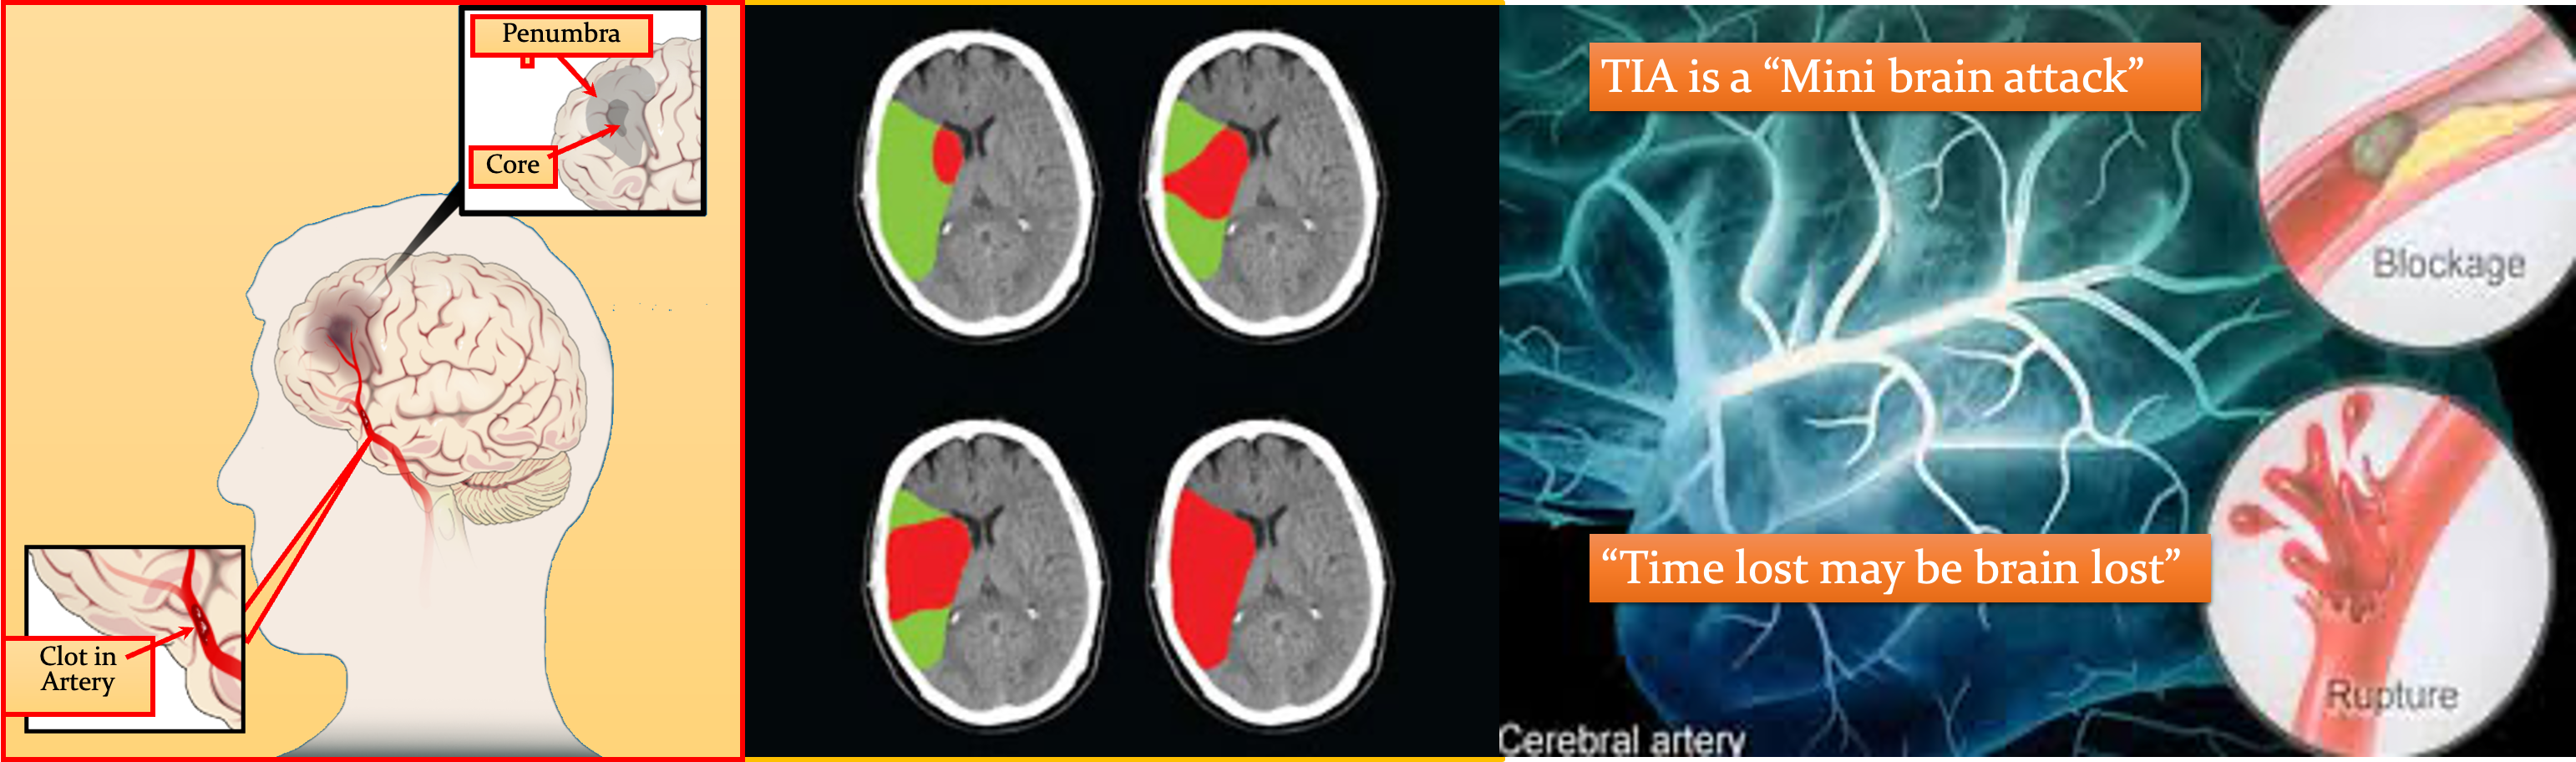

““TIME IS BRAIN: “SAVE THE PENUMBRA” Penumbra is zone of reversible ischemia around core of irreversible infarction—salvageable in first few hours after ischemic stroke onset

ISCHEMIC PENUMBRA

Immediately after an ischemic stroke (top left), a core of irreversibly damaged brain tissue (red) is surrounded by an area of viable but at-risk tissue called the penumbra (green). Unless blood flow is restored quickly, the tissue within the penumbra will be lost (bottom right).

TIA: symptoms “Mini stroke”

A transient ischaemic is caused by a temporary disruption in the blood supply to part of the brain. - Warning sign for stroke - Brief localized ischemia

Platelets (magnified here thousands of times) home to damaged areas of blood vessels and contribute to the formation of clots. Antiplatelet drugs can help reduce the risk of ischemic stroke.